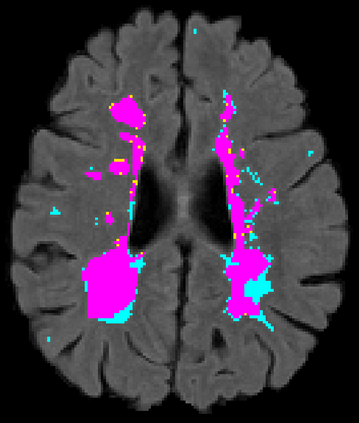

Recently, segmentation methods based on Convolutional Neural Networks (CNNs) showed promising performance in automatic Multiple Sclerosis (MS) lesions segmentation. These techniques have even outperformed human experts in controlled evaluation conditions such as Longitudinal MS Lesion Segmentation Challenge (ISBI Challenge). However state-of-the-art approaches trained to perform well on highly-controlled datasets fail to generalize on clinical data from unseen datasets. Instead of proposing another improvement of the segmentation accuracy, we propose a novel method robust to domain shift and performing well on unseen datasets, called DeepLesionBrain (DLB). This generalization property results from three main contributions. First, DLB is based on a large group of compact 3D CNNs. This spatially distributed strategy ensures a robust prediction despite the risk of generalization failure of some individual networks. Second, DLB includes a new image quality data augmentation to reduce dependency to training data specificity (e.g., acquisition protocol). Finally, to learn a more generalizable representation of MS lesions, we propose a hierarchical specialization learning (HSL). HSL is performed by pre-training a generic network over the whole brain, before using its weights as initialization to locally specialized networks. By this end, DLB learns both generic features extracted at global image level and specific features extracted at local image level. DLB generalization was validated in cross-dataset experiments on MSSEG'16, ISBI challenge, and in-house datasets. During experiments, DLB showed higher segmentation accuracy, better segmentation consistency and greater generalization performance compared to state-of-the-art methods. Therefore, DLB offers a robust framework well-suited for clinical practice.